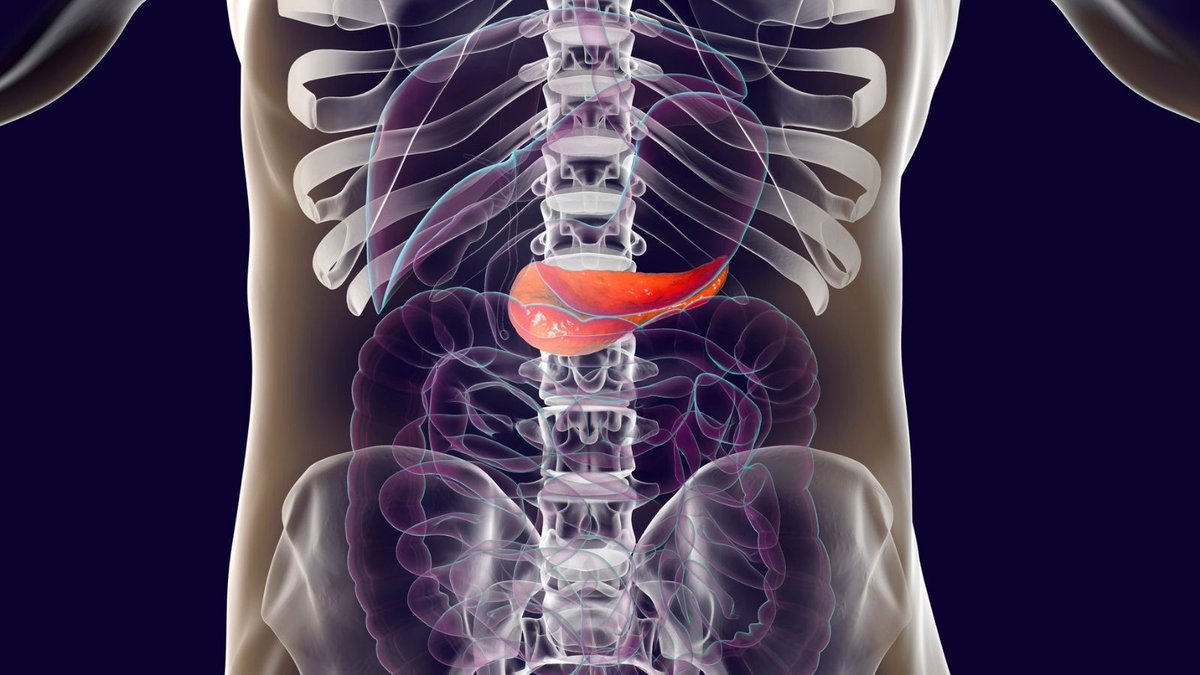

Análisis de las características clínicas de la pancreatitis aguda inducida por olanzapina

El objetivo del estudio fue explorar las características clínicas de la pancreatitis aguda inducida por olanzapina. La pancreatitis aguda es un efecto adverso raro de la olanzapina. Los médicos deben ser conscientes de tales complicaciones y controlar la pancreatina. Ther Adv Psychopharmacol. 2022